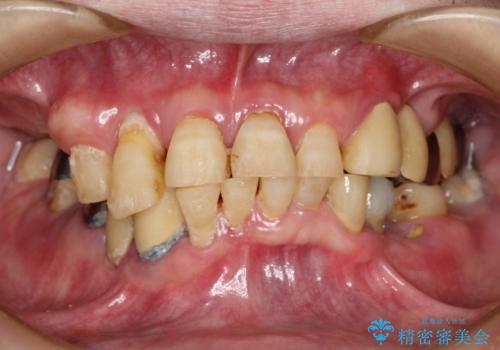

30代女性 前歯のオールセラミック

根管治療は問題なさそうでしたが、質の低いベニヤで修復されていたため、根管への漏洩予防・審美性回復の観点から6前歯をオールセラミックにてやり直すこととなりました。

仮歯での形態修正、ワックスモデルでの形態相談、技工士との連絡などを経て、現状可能な限り最高の審美修復ができたと思います。

被せものの種類:ジルコニアオールセラミック クラウン スペシャル